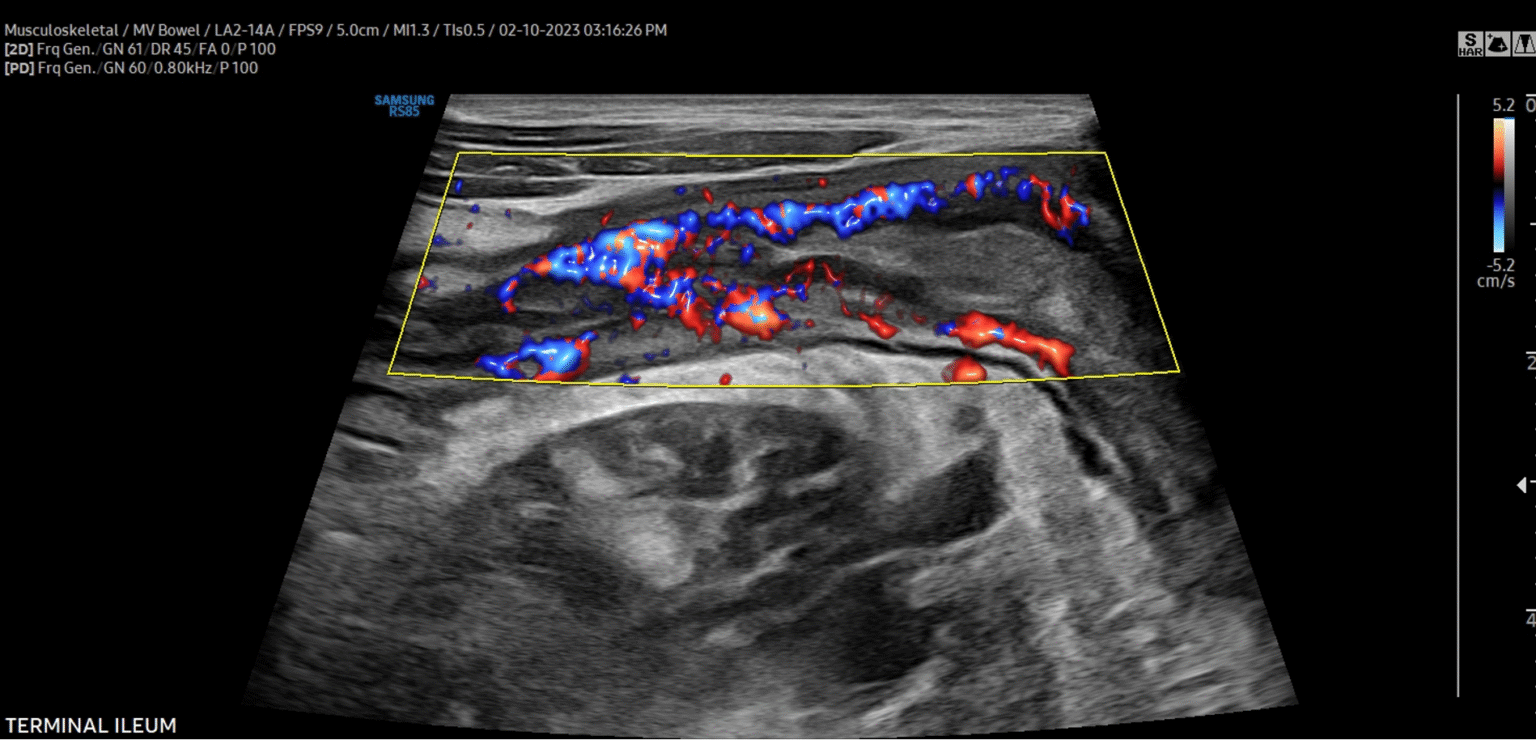

Intestinal ultrasound is a safe, non‑invasive imaging test that uses sound waves to create detailed pictures of the intestines. Unlike CT scans or X‑rays, it does not expose patients to radiation and can be repeated when needed.

It is especially useful for diagnosing and monitoring conditions like Crohn’s disease, ulcerative colitis, and other bowel disorders.

The doctor moves the handheld ultrasound probe across the abdomen, capturing detailed images of the intestines on a monitor.

The gastroenterologist examines the images in real time to look for inflammation, thickening, obstructions, or other abnormalities.